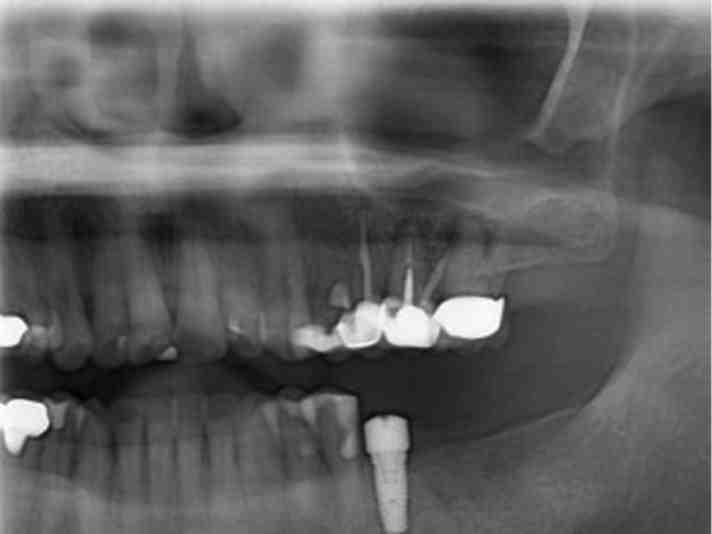

What type of radiograph is best for placing dental implants and why?

Periapical radiography is used to find the presence of pathos and the location of anatomical structures around the implant site and to assess the implant after surgery.